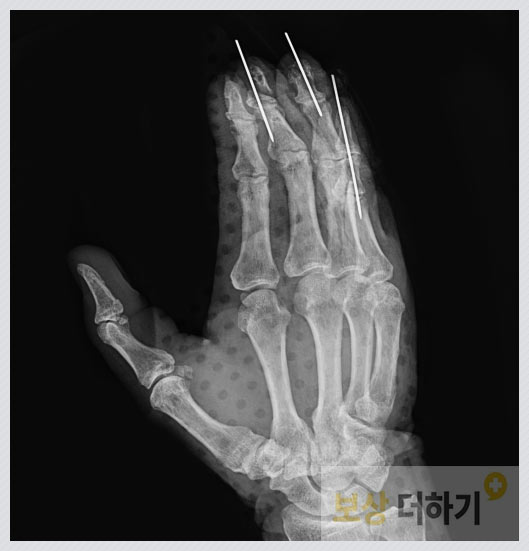

손가락은 일터에서, 일상생활에서 가장 많이 다치는 신체 부위 중 하나입니다. 혹시 여러분들도 다음과 같은 관혈적 정복 및 내고정술 받으셨나요?

진단명 ● 3, 4, 5수지 압궤상 · 골절 ● 5수지 건파열 오른쪽 세 번째부터 새끼손가락까지 모두 골절되고 연부 조직이 손상되어 수술을 받으셔야 했습니다.

수술 치료 ● 관혈적 정복 및 내고정술 ● 변연 절제술 및 국소 피판술 ● 복합조직 이식술 ● 건봉합술